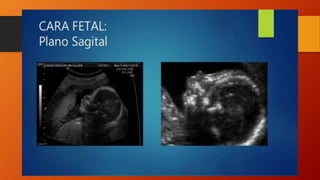

CARA Perfil, columna ylabio superior • Las estructuras anatómicas faciales se pueden identificar desde la semana 12. Las estructuras a valorar son: • • Frente • • Orbitas • • Nariz • • Labios • • Orejas ANATOMIA NORMAL • Un corte medio sagital nos permite visualizar el perfil fetal. • El plano coronal es el más importante en la evaluación de la integridad facial. • En este corte se pueden visualizar las órbitas, labios y nariz.

cortes Corte sagital decara para evaluar perfil del feto. – Morfología de frente, nariz, labios y mentón. Corte coronal (mas importantes), para evaluar integridad facial – A nivel de orbitas para medición de distancia orbitaria – Plano frontocoronal tangencial: nariz, labios, y mentón. Corte transversal: estudio de paladar